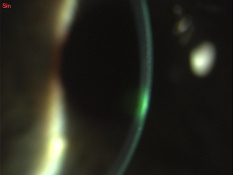

(fig.5) La lente appoggia all’apice del cono e si rileva anche un elevato anello d’appoggio alla sua base che garantisce lo scarico del peso lente-palpebra

Nella speranza di ridurre la spinta meccanica di tipo trazionale ho provato lenti RGP semi-sclerali. Con l’ausilio del set di prova ho cercato di trovare il miglior compromesso d’appoggio verificando i vari sollevamenti delle flangie e modificandone i raggi al fine di mantenere sotto la lente un sollevamento assiale non superiore ai 70-90 µ. La lente ordinata come inizio è stata la seguente: Lente tipo M semisclerale Opto Kontakt K.L. srl D. 12,80 rb 7,25 p. dk 100 La lente soggettivamente è stata molto ben tollerata e il visus raggiunto è stato di 9\10 (fig. 5).